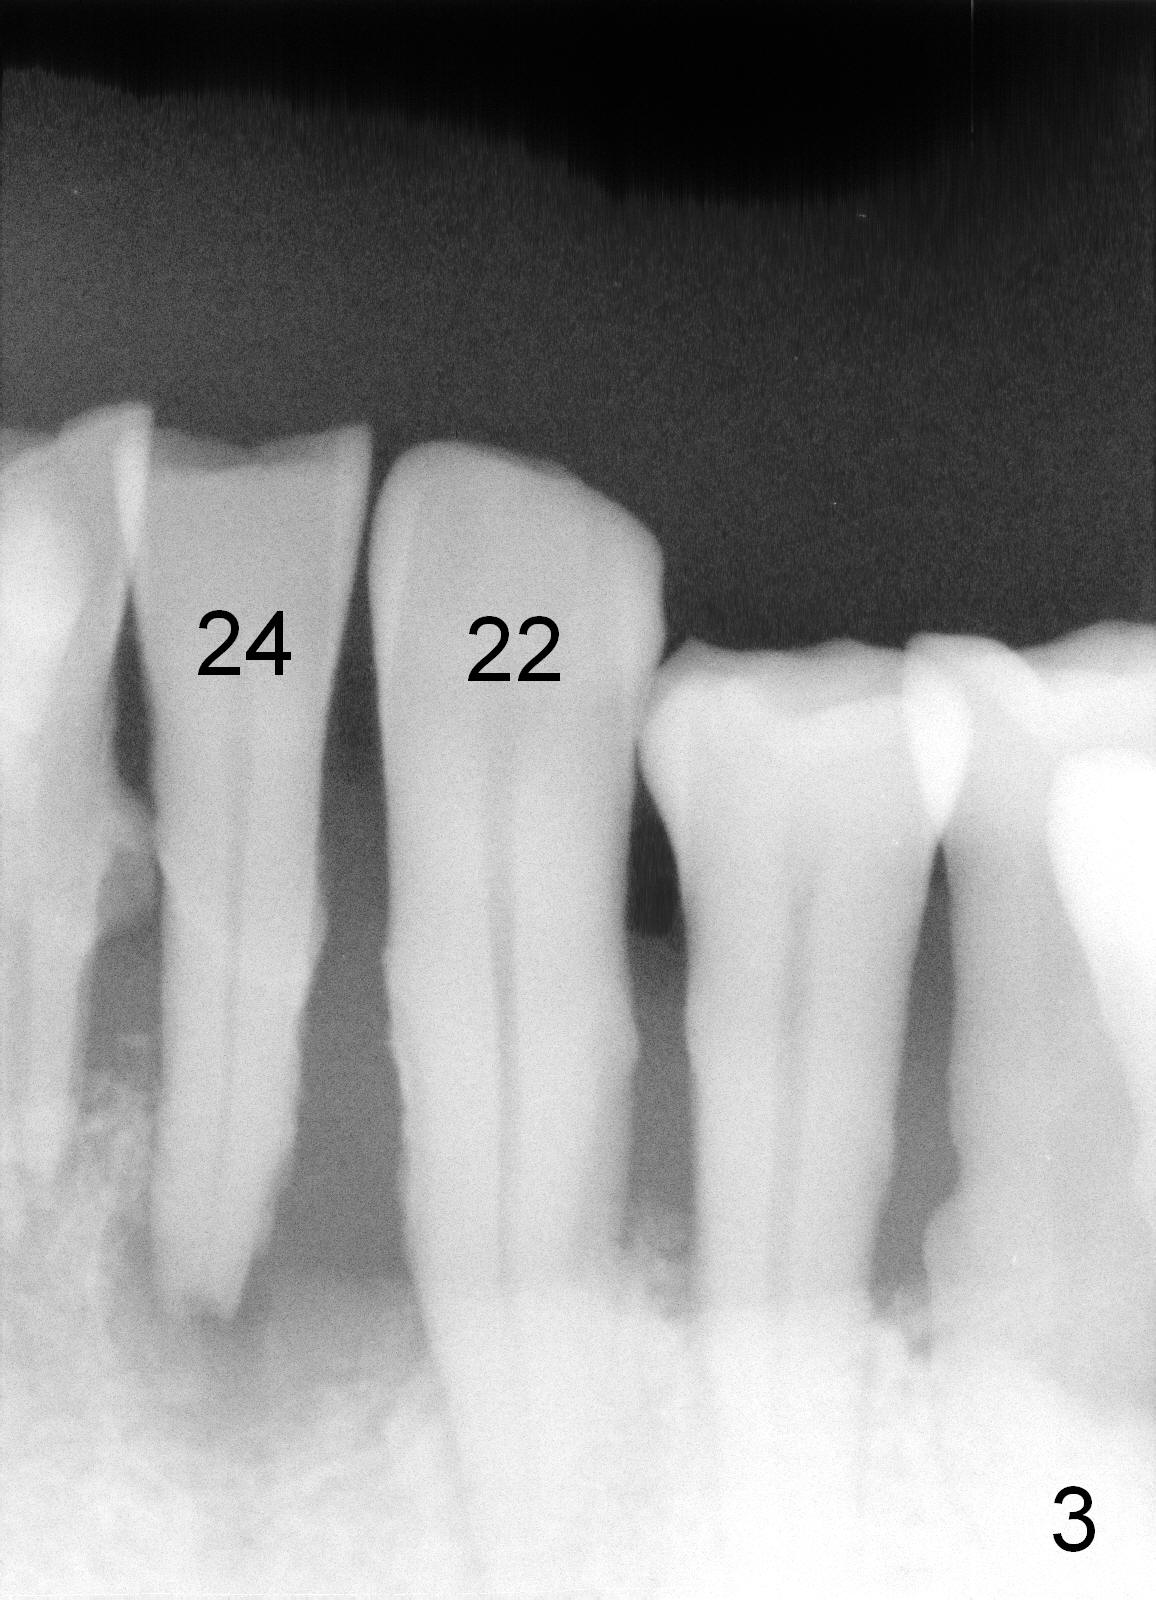

A 62-year-old man (CZ) has severe generalizd chronic periodontitis and occlusal trauma. Full mouth extraction and reconstruction is required. The patient prefers extraction by stage. The lower anterior segment reconstruction is our first treatment: from #22-28. The tooth #28 is exfoliated now (Fig.1 (full mouth X-ray was taken 4 years ago), 5). There are 3 incisors left. Two-piece implants are going to be placed for the canines and premolar, while 2 of 1 piece implants in the incisor sockets (treated with Metronidazole with Epinephrine gauze) for a bridge (Fig.2). Straight 1 piece 3 mm implants are routinely placed, whereas angled or 2.5 mm ones are backup. Two of 1.2 mm pilot drills and 3 of marked parallel pins may be needed.